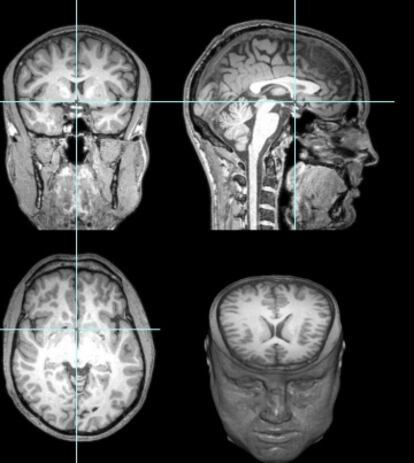

Un año antes de la proeza, Garéyev se prestó a que su cerebro -dividido en 200 áreas- fuera profundamente analizado por el equipo del doctor Jesse Rissman, director del Laboratorio de Memoria de la Universidad de Los Ángeles (UCLA). Esas pruebas forman parte de un estudio mucho más amplio que aún no ha sido publicado, pero Rissman ha desvelado algunos resultados. La conclusión más asombrosa para quienes llevamos muchos años informando sobre ajedrez a ciegas es que la memoria fotográfica de Garéyev no es extraordinaria: “No encontramos nada excepcional en las pruebas convencionales que pasó Garéyev en cuanto a su capacidad para memorizar números, fotos o palabras en un orden concreto”, asegura Rissman, quien sin embargo se muestra “muy asombrado por el número de partidas que puede mantener activas en su memoria simultáneamente”.

Entonces, ¿dónde está la clave? En que varias partes del cerebro de Garéyev, especialmente en la zona frontoparietal, están mucho mejor conectadas que en la gran mayoría de las personas, según se desprende del escaneo que le hicieron en la UCLA. “Utilizamos esa red de conexiones en casi todas las tareas complejas. Nos ayuda a centrar la atención, recordar instrucciones o normas y decidir si respondemos o no a una pregunta o estímulo”, explica Rissman. Además, los expertos de la UCLA descubrieron que la visión espacial de Garéyev está excepcionalmente desarrollada, porque la parte del cerebro que la controla tiene muchas conexiones con otras.

Tras conocer el avance de los resultados del estudio de Rissman, Maestú deduce: “Garéyev debe tener un desarrollo excepcional de lo que llamamos agenda viso-espacial de la memoria operativa, la que nos sirve para recordar información durante periodos cortos de tiempo, no durante meses o años. Esa función depende de los lóbulos central y parietal, que están alojados en la parte derecha del cerebro. En otras palabras, lo asombroso en este caso no es que recuerde mucho, sino que maneja lo que recuerda de manera excelente, mucho mejor de lo habitual”.